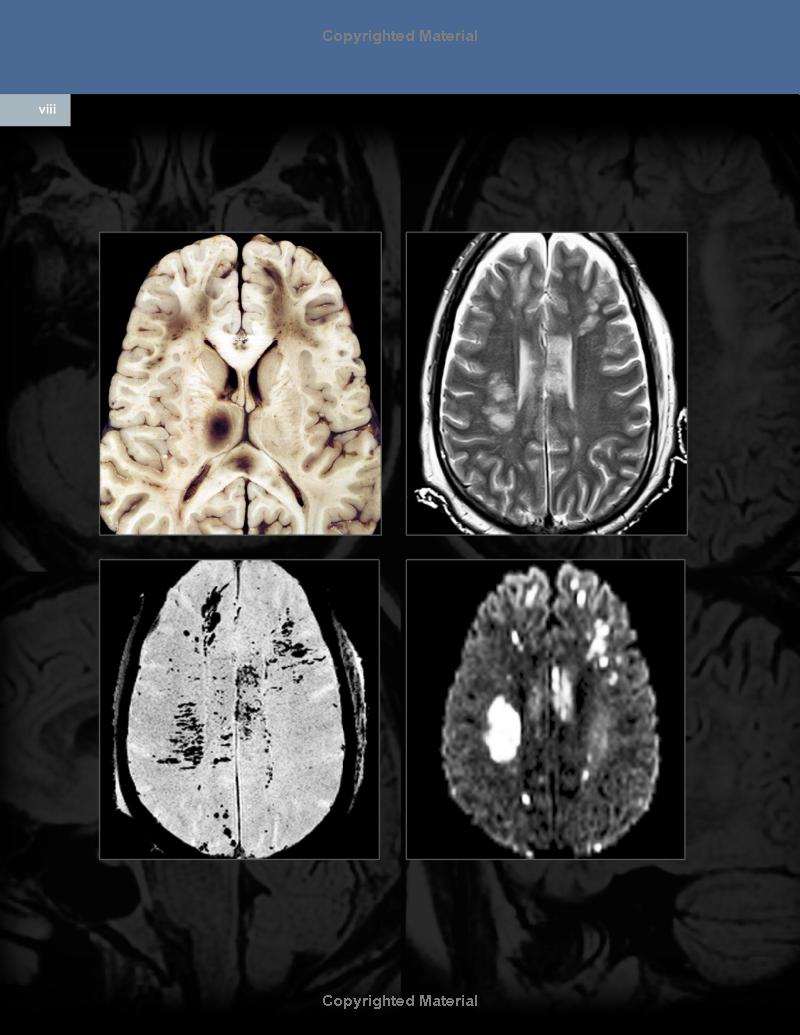

Comprehensive, visually appealing, and easy to understand, Osborn’s Brain, second edition, by the highly esteemed Dr. Anne G. Osborn, provides a solid framework for understanding the complex subject of brain imaging when studied cover to cover. Almost completely rewritten and featuring 75% new illustrations, it combines essential anatomy with gross pathology and imaging, clearly demonstrating why and how diseases appear the way they do. The most immediate emergent diagnostic topics are followed by nonemergent pathologies, integrating the most relevant information from Dr. Osborn’s entire career of accumulated knowledge, experience, and interest in neuropathology, neurosurgery, and clinical neurosciences.

- Features more than 4,000 stunning, high-resolution radiologic images and medical illustrations, all of which are annotated to describe the most clinically significant features